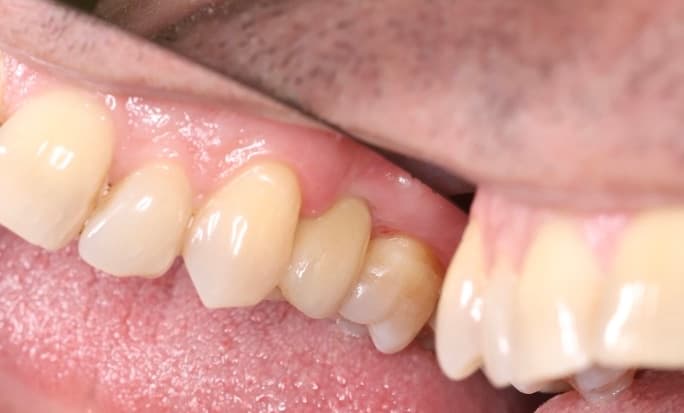

Восстановление бокового зуба, разрушенного менее чем на 1/2